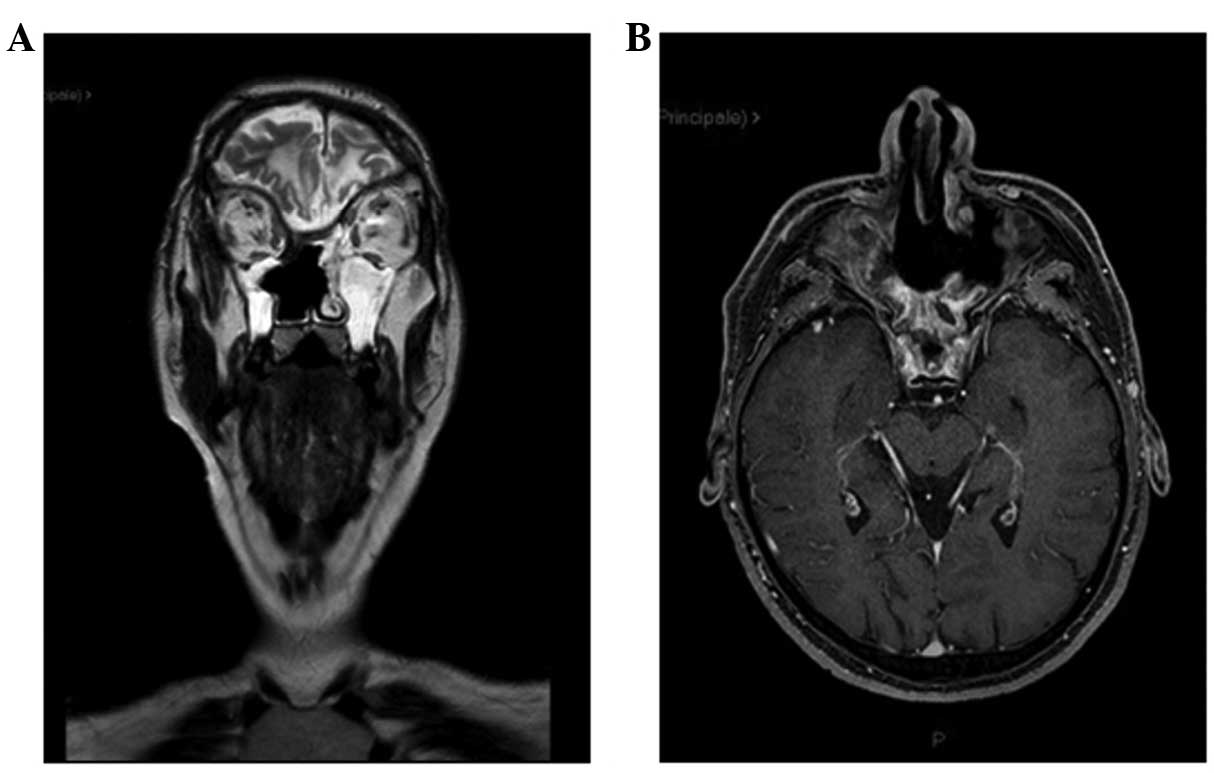

Ewing's sarcoma (ES) is an aggressive tumour that may present with skeletal and extraskeletal forms. The extraskeletal form is rarely encountered in the head and neck region and is extremely rare in the sinonasal tract. This is the case report of a ES of the ethmoid sinus with intracranial and orbital extension in a 33‑year‑old male patient who presented with anosmia, epistaxis, reduction of visual acuity in the left eye and headache. On otorhinolaryngological clinical examination and biopsy via flexible endoscope, the lesion was misdiagnosed as ethmoid sinus carcinoma. The subsequent magnetic resonance imaging (MRI) of the brain revealed a large mass (6x7 cm) eroding the ethmoid and sphenoid sinuses, extending beyond the orbits and occupying the anterior cranial fossa with a maximum extension of ~5 cm. The patient underwent surgical resection and the microscopic examination of the specimen established the diagnosis of ES (immunohistochemically positive for CD99, neuron‑specific enolase, CD56, synaptophysin, pancytokeratin, low‑molecular weight cytokeratins and vimentin. The periodic acid Schiff stain exhibited strong intracytoplasmic block positivity and fluorescence in situ hybridization revealed a t(22;11) translocation. first‑line chemotherapy was administered for 3 cycles; however, on restaging MRI, local disease progression was diagnosed. The patient received radiotherapy and second‑line chemotherapy for 6 cycles. At 15 months after the diagnosis, the patient remains recurrence-free and maintains a good functional status and quality of life.